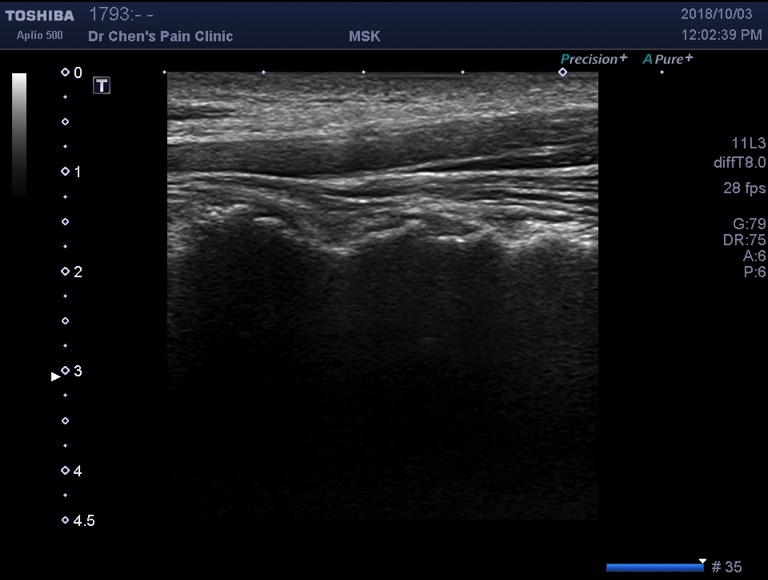

頸椎關節炎的診斷相對簡單,醫師使用觸診技巧找出患者頸部特別疼痛的位置,然後使用超音波確認疼痛位置下方是哪一個頸椎關節發炎。在確認正確的位置之後,可以先